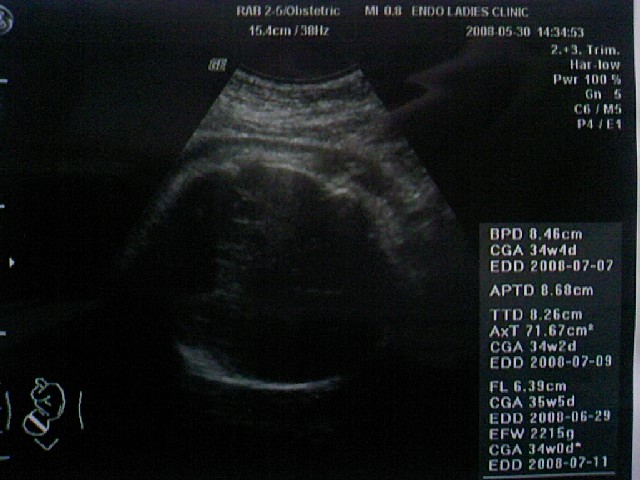

逆子ちゃん治ってましたぁーーー!!!!

女の子

でしたぁぁぁぁ~~~

推定体重は・・・ 前回1799g → 今回2215g と順調な大きさ